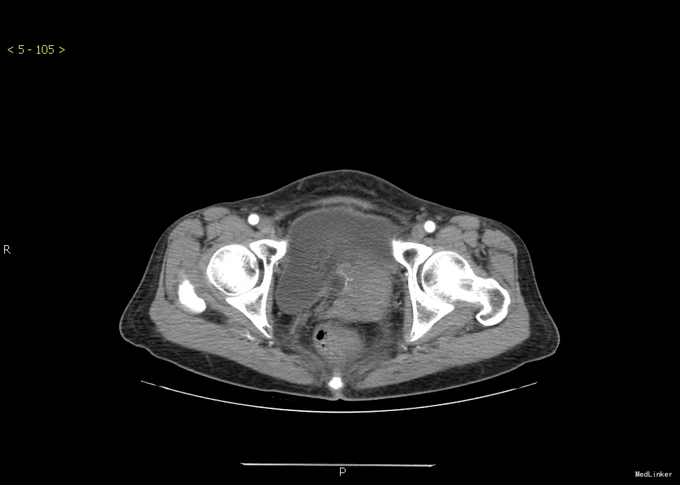

查体:腹部膨隆,腹部张力大,无压痛,无反跳痛,移动性浊音阳性。其余无特殊。 胸部+全腹部CT示:1.胸部增强扫描未见明确异常。2.盆腔底部腹膜明显不规则增厚,右侧附件可见肿块,考虑卵巢肿瘤可能。3.腹盆腔大量积液。

诊断:卵巢钎维瘤合并麦格综合征 治疗:行腹腔积液引流后,腹水未发现肿瘤细胞。后行全子宫双附件切除术。术后病理提示:卵巢纤维瘤。手术顺利。